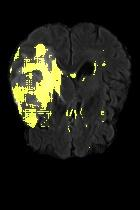

Current unsupervised anomaly localization approaches rely on generative models to learn the distribution of normal images, which is later used to identify potential anomalous regions derived from errors on the reconstructed images. However, a main limitation of nearly all prior literature is the need of employing anomalous images to set a class-specific threshold to locate the anomalies. This limits their usability in realistic scenarios, where only normal data is typically accessible. Despite this major drawback, only a handful of works have addressed this limitation, by integrating supervision on attention maps during training. In this work, we propose a novel formulation that does not require accessing images with abnormalities to define the threshold. Furthermore, and in contrast to very recent work, the proposed constraint is formulated in a more principled manner, leveraging well-known knowledge in constrained optimization. In particular, the equality constraint on the attention maps in prior work is replaced by an inequality constraint, which allows more flexibility. In addition, to address the limitations of penalty-based functions we employ an extension of the popular log-barrier methods to handle the constraint. Comprehensive experiments on the popular BRATS'19 dataset demonstrate that the proposed approach substantially outperforms relevant literature, establishing new state-of-the-art results for unsupervised lesion segmentation.